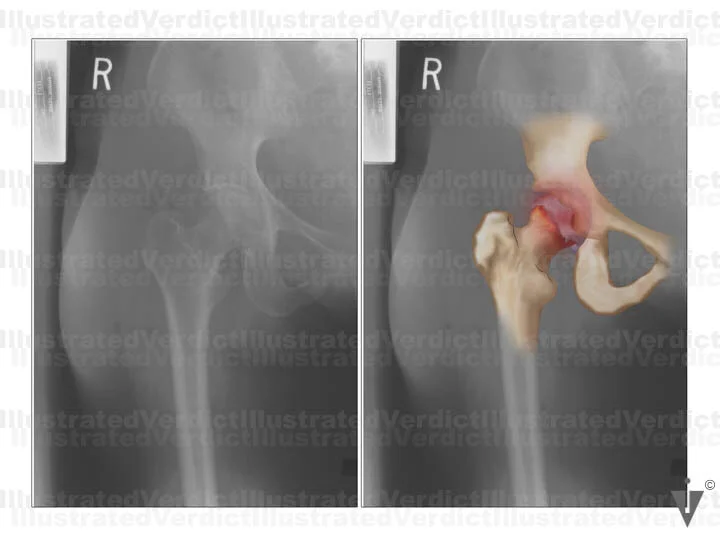

BOARD 7

1. Film enhancement of avascular necrosis in femur